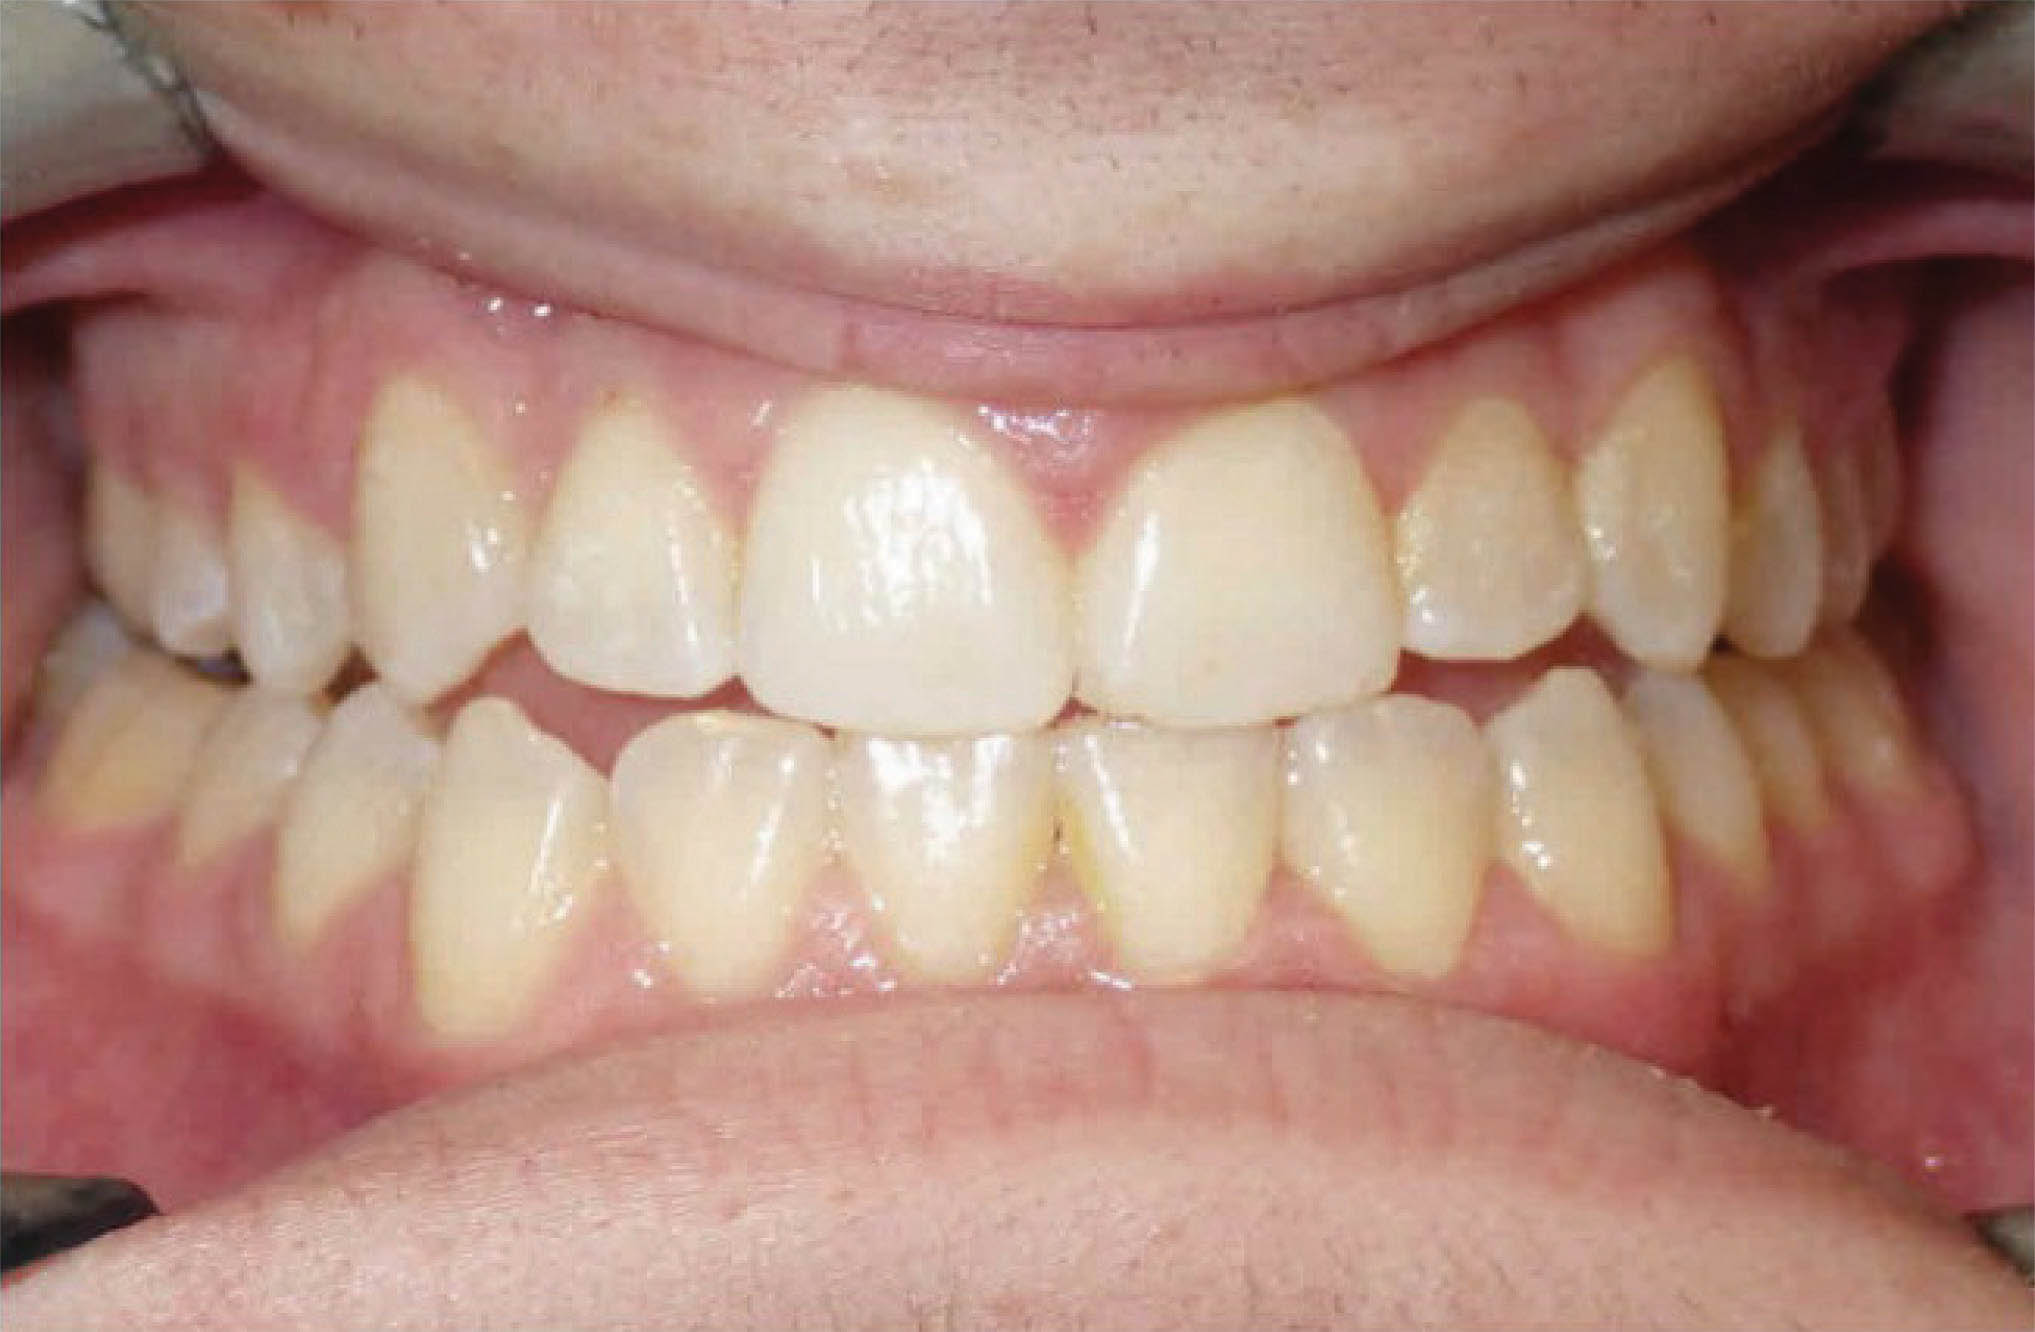

: اصلاح اورجت

سومین کاربرد استریپ اصلاح اورجت در بیماران کلاسII یا III است. اکلوژن بیمار شکل 147-6 کلاسIII است. در این بیمار از پایین استریپ کردیم تا با حرکت خلفی قدامیها به اورجت مطلوب و رابطه کانینی کلاسI برسیم. البته در این بیمار از الاستیک کلاسIII هم استفاده گردیده است. استریپ خلفی در هر دو سمت انجام گردید.

نتایج درمان در شکل 149-6 مشخص است.

شکل 147-6

شکل 148-6

شکل 149-6